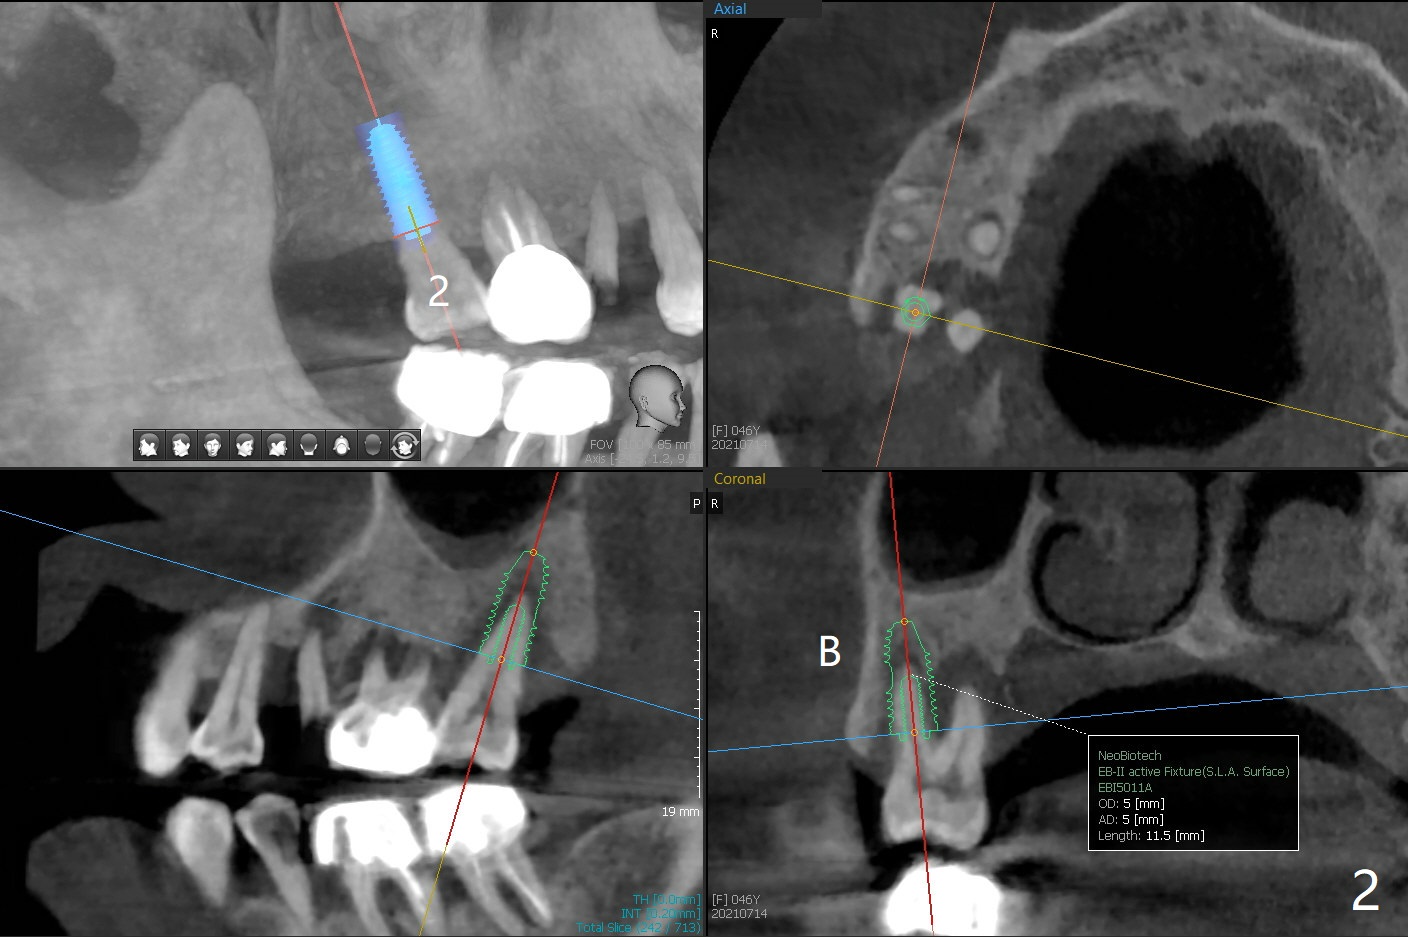

Away From Lesion

A 46-year-old woman wants to extract the mobile #2 and residual root of #4 for implants. She wants to save the tooth #3 with mobility II (Fig.1). Place an implant at #2 away from #3 (Fig.2). A small implant will be placed at #4 for the best possible trajectory (Fig.3). PRFx2.